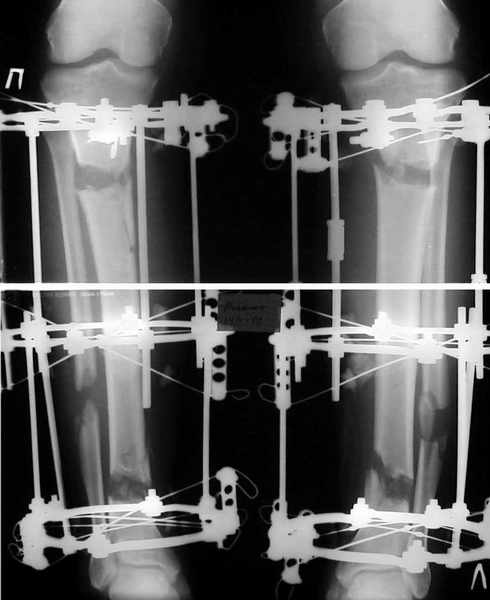

В приложении - промежуточные рентгенограммы пациента, которому я

недавно увеличил рость со 183 до 190 см.

См рентгенграмму.

Еще раз см. рентгенограмму :))

Кликните для загрузки файла double1.jpg

24KB (24908 bytes)